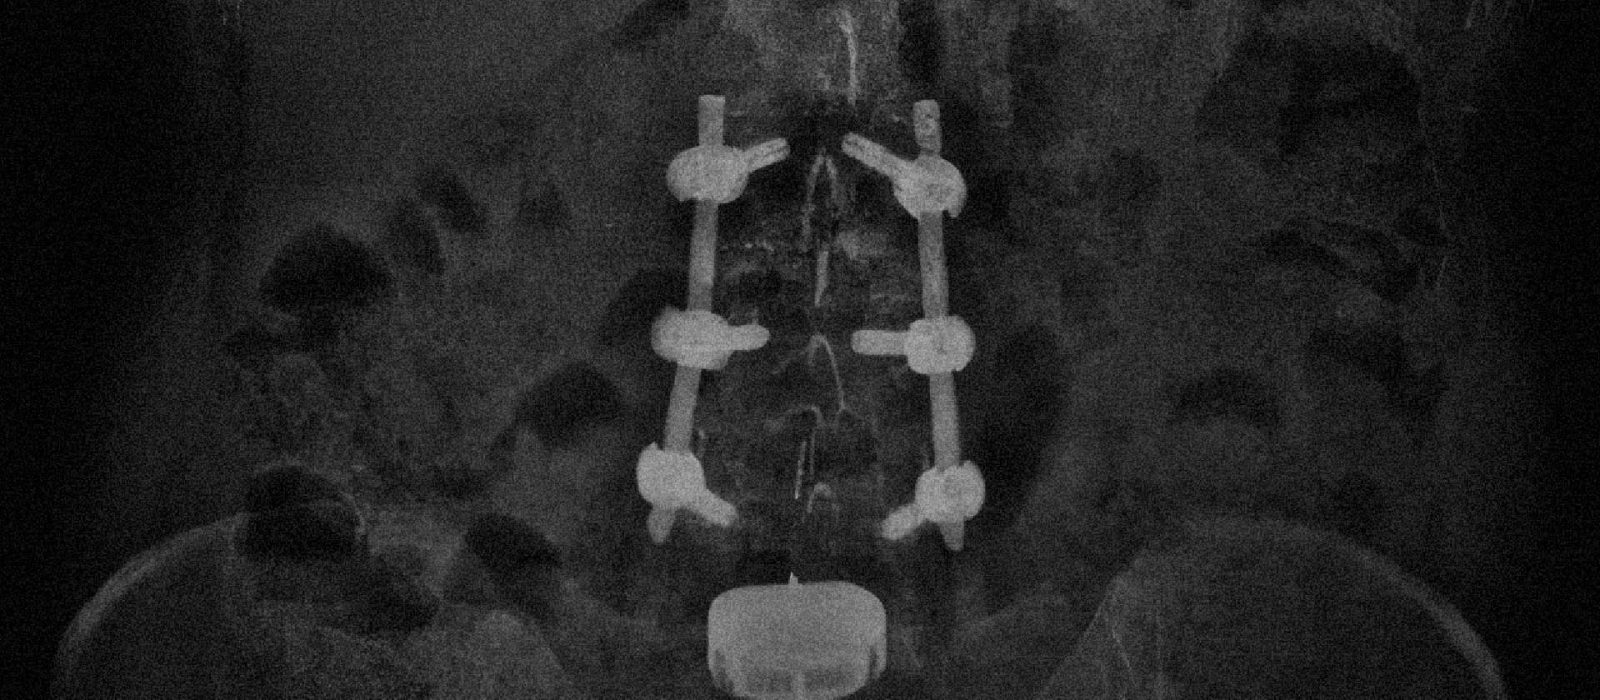

En esta edición, con el Dr. Rodrigo Pons Belmonte como editor invitado, contamos con la colaboración de colegas trasandinos que se suman a nuestros contenidos con una mirada sobre la cirugía de columna en Chile. Factores de riesgo en el manejo conservador de fracturas facetarias cervicales subaxiales. Evolución de la cirugía endoscópica en Chile: un cambio de paradigma en la formación. Encuentros binacionales Argentina-Chile en cirugía de columna. Caso clínico: Artrodesis 360° MISS en patología lumbar degenerativa. Además: Filiales SAPCV, Fellowships en primera persona, experiencias internacionales y cobertura de eventos.